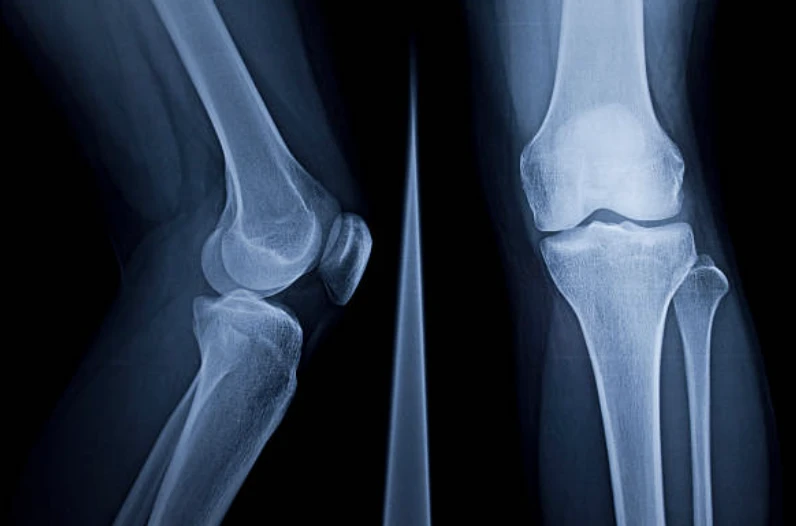

- 무릎 부상에 대해서 병원 진료를 받을 때는 일반적으로 X-레이, MRI, CT 스캔 또는 관절경과 같은 진단 절차가 진행될 수 있습니다.

- 엑스레이(X-ray) : 눈에 보이지 않는 전자기 에너지 빔을 사용하여 내부 조직과 뼈 및 장기에 대한 사진을 필름에 만듭니다.